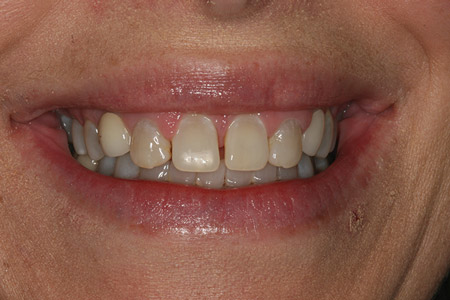

A comprehensive cosmetic, radiographic, and functional evaluation was performed.1 The patient was able to identify the major concerns leading to her dissatisfaction with her smile, including the presence of multiple diastemata, tooth proportion improprieties, unnatural emergence profile of her implant restorations, and her desire for a whiter smile (figure 3).2

Figure 3